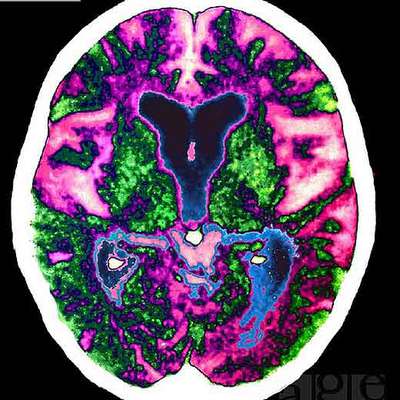

Pero la gran esperanza no está en retrasar los síntomas. Está en atacar la causa de la enfermedad, y en este punto, ¿qué puede esperar los enfermos como Maragall de la investigación en curso? Teresa Gómez Isla se encuentra en las más avanzadas trincheras, y aunque, como buena científica, huye del triunfalismo, de su explicación se deduce que hay fundados motivos para el optimismo. "En los últimos años hemos aprendido mucho de cómo se forman las lesiones", dice, "y esto va a dar sus frutos". Algunos pronostican que en cinco años aparecerán las primeros fármacos contra dianas terapéuticas específicas. Ella no se moja respecto al tiempo, pero así están las cosas: se sabe que el proceso se inicia, tal vez décadas antes del primer olvido, con una acumulación anormal de una proteína presente en el cerebro, la beta amiloide. Estas acumulaciones interfieren con la comunicación entre neuronas y acaban afectando también a su propia estructura, propiciando la formación de unos ovillos neurofibrilares que acaban provocando su propia muerte. Conforme avanza la enfermedad, la pérdida de neuronas va afectando a diferentes funciones hasta comprometer toda la actividad cerebral intelectual y funcional.

La muerte neuronal comienza por el hipocampo y se va extendiendo por toda la corteza cerebral. Por eso, el alzhéimer es como una vuelta atrás en la vida, como si las manecillas del reloj comenzaran a correr en sentido contrario, de manera que la persona va perdiendo, una por una, las capacidades intelectuales y habilidades en el orden inverso al que las adquirió desde que era un feto. Y de hecho, a muchos enfermos la muerte les sorprende en posición fetal, sin ningún control sobre su cuerpo y totalmente desconectados del mundo exterior.